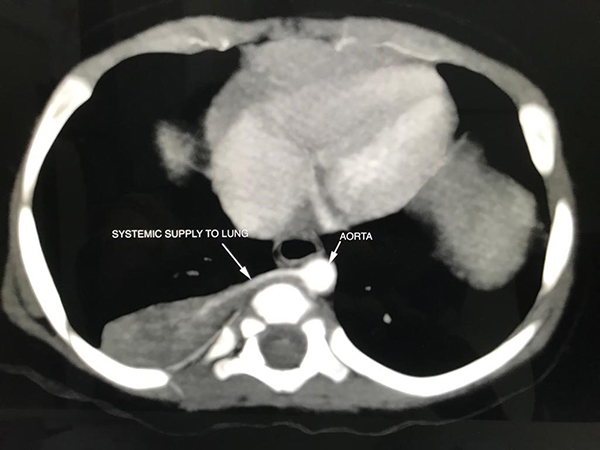

Clinical History: A 9-month-old asymptomatic girl underwent a right postero-lateral thoracotomy with excision of a right-sided (antenatally identified) non-functioning lung segment, which was demonstrated to have a systemic blood supply on preoperative imaging (Figure 1). On gross examination, the specimen measured 45 × 30 × 08 mm, was completely covered by pleura externally and showed yellowish firm areas and tiny cysts measuring 1-5 mm on cut section (Figure 2). H&E stained sections from the lung segment are shown at varying magnifications (Figures 3-6).

PSs are localized lesions showing both bronchopulmonary and vascular anomalies. They are extremely rare, with no published population incidence. In these lesions, the non-functioning lung parenchyma receives its blood supply via an aberrant systemic artery and continuity of the lesion with the upper respiratory tract cannot be demonstrated. PSs are further classified as extra-lobar (EPS) or intra-lobar (IPS), the former being invested by its own pleura. CPAM also called congenital cystic adenomatoid malformation (CCAM) is considered to be primarily a bronchopulmonary anomaly. The incidence ranges from 1 in 11,000 to 1 in 35,000 live births. It is characterized by the presence of anomalous bronchiolar or acinar structures. Since the lesion may or may not be cystic, the former term is preferred over the latter. These lesions are generally poorly delineated from the adjacent normal lung parenchyma.